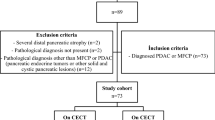

The inclusion flow chart is displayed in Fig. 2. We examined 33 CF patients and 25 healthy controls according to the protocol. We excluded 8 CF patients and 5 controls due to poor pancreatic ultrasound visualisation, or failure to track the same region of interest throughout the examination. Accordingly, we present results from 25 CF patients and 20 healthy controls (HC). When sorted by exocrine pancreatic function, patient groups were divided as follows: Cystic fibrosis; pancreatic insufficient (CFI, n = 13) and cystic fibrosis; pancreatic sufficient (CFS, n = 12). Observer 2 failed to achieve analysis for four of 45 subjects analysed by observer 1. Further three analyses were excluded from the analysis performed by observer 2 due to non-physiological values (MTT > 15 s), leaving 38 analyses for the interrater agreement analysis. Demographic data and data for exocrine function are displayed in Table 1. The control group was slightly older and contained more females than the CF groups (p < 0.05).